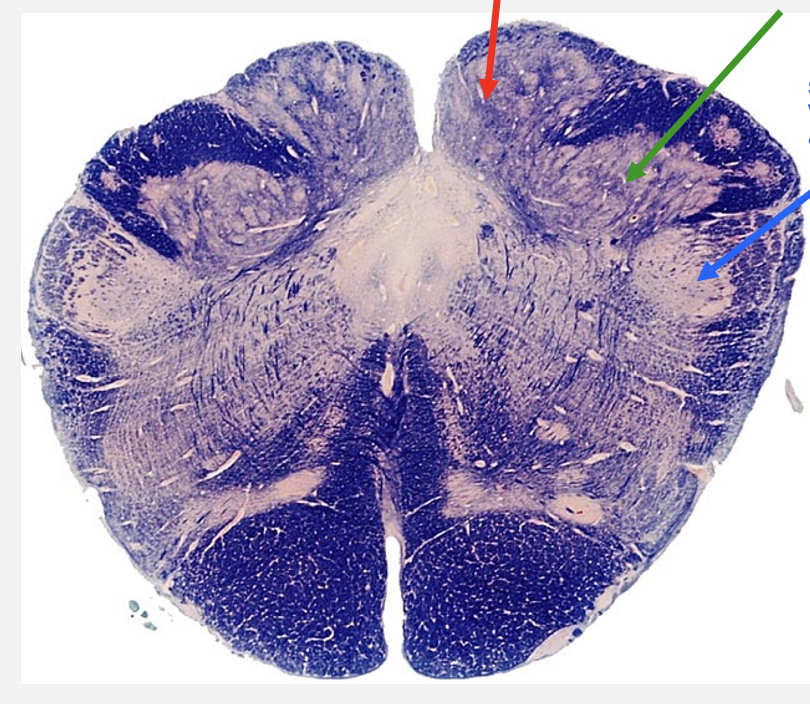

spino-medullary junction cross section structures

nucleus garcilus

gracile tubercle

fasiculus gracilus axons synpase in BLANK BLANK to form the BLANK BLANK

nucleus cuneatus

cuneate tubercle

fasiculus cuneatus axons synapse in BLANK BLANK to form the BLANK BLANK

spinal nucleus of V

trigeminal tubercle

spinal tract of V axons synpase in BLANK BLANK BLANK BLANK to form the BLANK BLANK

nucleus gracilus

spinal tract of V